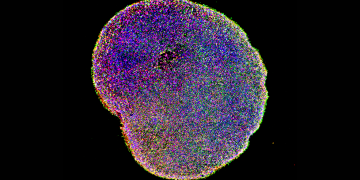

Leggi di piùAd Harvard creati cervelli in vitro utili per la sperimentazione

Produrre in laboratorio dei mini-cervelli per poter studiare e curare malattie neurologiche quali l'autismo o la schizofrenia. Già, quello che era una chimera fino a pochi anni fa, ora potrebbe...